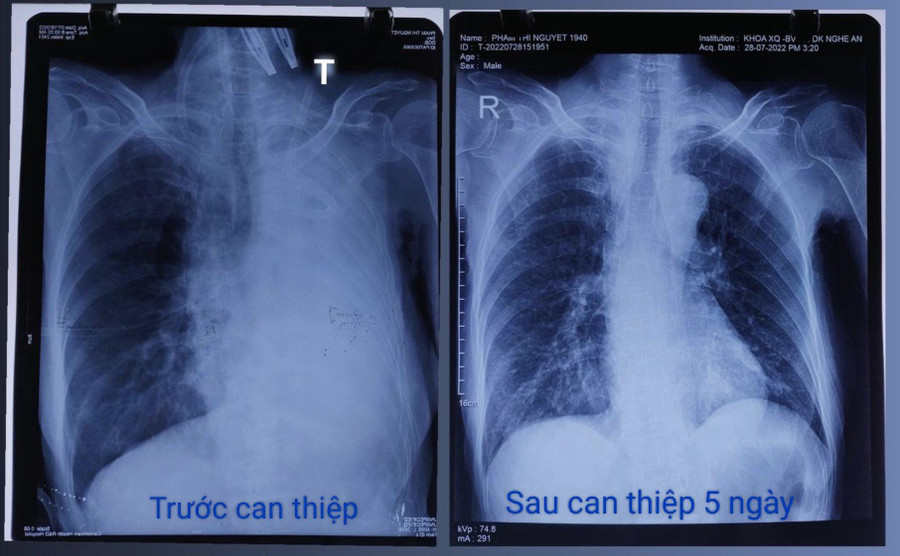

![]() |

| Sau can thiệp, sức khoẻ bệnh nhân khi xuất viện về nhà đã ổn định. Ảnh: BV. |

Sau nội soi, bệnh nhân được hồi sức tích cực ngoại khoa 4 ngày, chuyển Khoa Nội dị ứng hô hấp điều trị 1 tuần. Đến nay, sức khỏe bệnh nhân sau xuất viện về nhà đã ổn định.